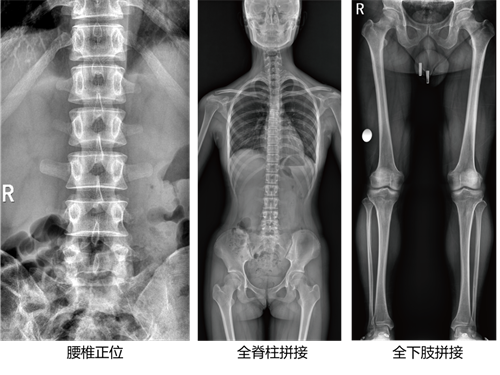

不同于常规静态DR只能进行平片摄影检查,动态DR可以实现多模态的检查。包括数字化摄影、数字化透视、数字化造影、可视化点片、尘肺筛查、断层融合功能检查、DSA功能检查、全脊柱及双下肢拼接检查、动态功能成像等多模态检查,相较于静态DR具有更加丰富的临床应用。不止可以应用于放射科,还可以应用于体检科、内科、外科、骨科、急诊科等,应用的科室更加广泛。

动态DR是所有新技术应用的生态平台,相比静态DR拥有更加广阔的发展空间和更加前沿的新技术,现在包括GE、西门子、安健科技等各大行业顶尖医疗器械公司都在往动态DR上的发展,所有DR的新技术,包括能谱技术、动态功能化成像技术、WR-3D负重位锥形束CT摄影、断层融合扫描摄影等都需要动态DR作为基础,而这些新技术早已经在医疗检查中不可或缺,并且得到医院的一致认可,而静态DR则无法支撑以上新技术。